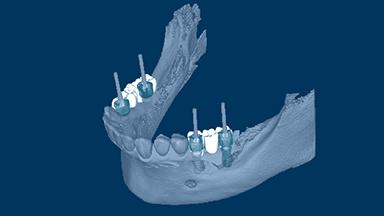

Principles of Computer-Aided Implant Planning

Prosthodontically driven implant planning ensures that implant placement is compatible with the desired end result, which is a key factor for successful outcomes in implant therapy.

Digital technologies now available in the field of implant dentistry facilitate prosthodontically driven implant planning. Benefits of these technologies include significant improvements in patient assessment and treatment planning, allowing clinicians to position supporting implants with a high degree of accuracy.

This Learning Module will discuss the routine use of computer-based planning for implant placement.